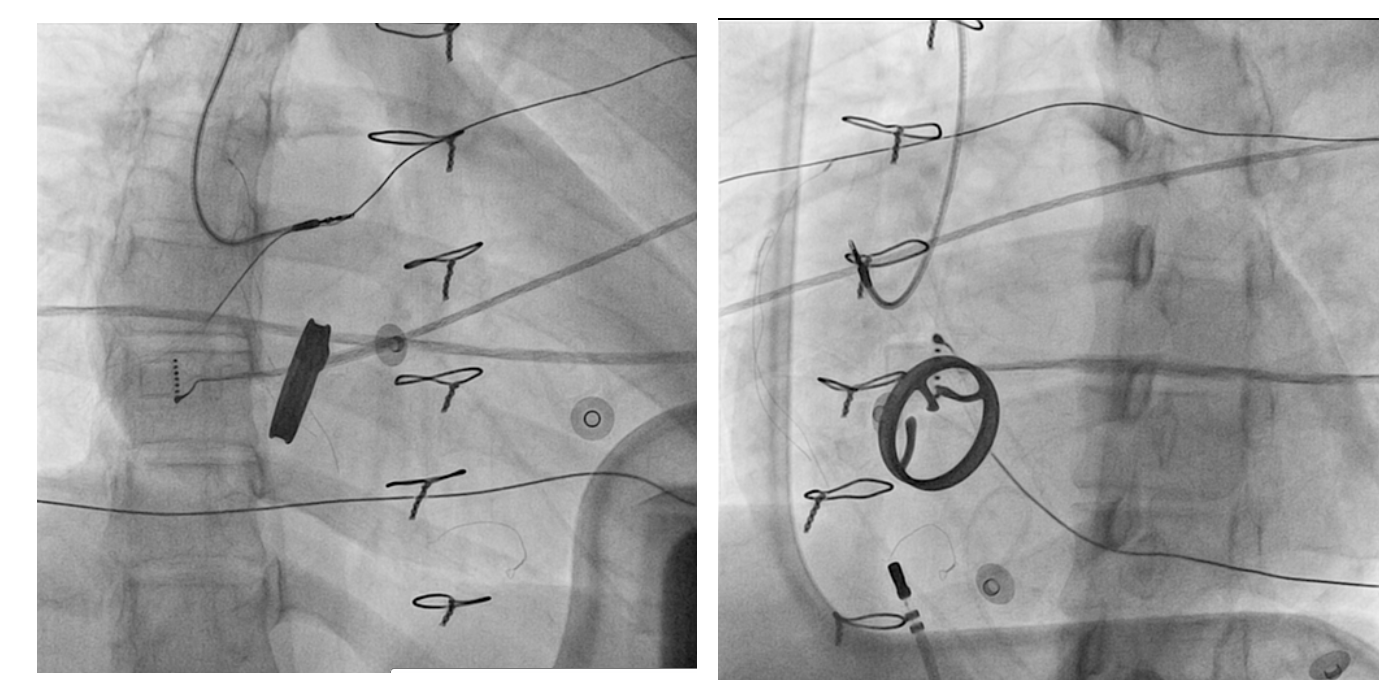

Hardware

Multi electrode catheter

catheters.jpg

Deflectable Sheath

sheaths.jpg

Multi Electrode Mapping

multipoint_catheters.jpg

Imaging

• CT merge

• ICE - With or without integration